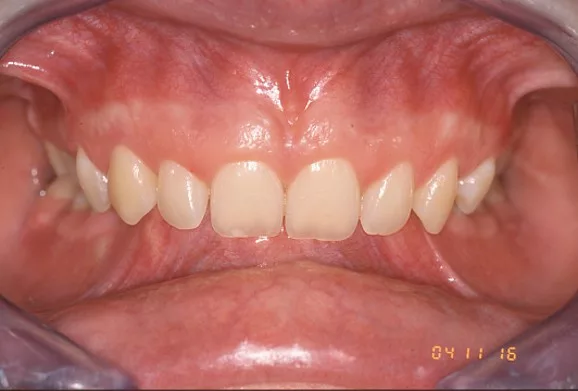

Il existe de nombreuses variétés de Classe II squelettiques. Parmi les plus fréquentes, on distingue les Classe II squelettiques avec surplomb des incisives supérieures (Classes II Division 1) et les Classes II squelettiques avec recouvrement des incisives inférieures par les incisives supérieures (Classes II Division 2).

Classe II Squelettique Division 2 :

Classe II Squelettique Division 2